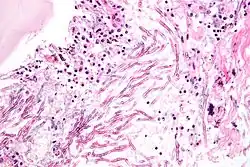

Аспергиллёз лёгких

Аспергиллёз — группа заболеваний, вызываемых грибами рода аспергилл. Наиболее распространённый подтип инфекций придаточных пазух носа, ассоциируемый с аспергиллёзом, вызывается видом A. fumigatus[22]. Симптомы включают жар, кашель, боль в груди или диспноэ (одышку), что также проявляется и в случае многих других заболеваний и поэтому может усложнить диагностику. Обычно восприимчивы только пациенты с уже ослабленной иммунной системой или страдающие от других болезненных лёгочных состояний. Главными формами заболевания у человека являются[23][24]:

• аллергический бронхолёгочный аспергиллёз, поражающий больных с респираторными инфекциями, такими как бронхиальная астма, муковисцидоз (кистозный фиброз), и синусит;

• острый инвазивный аспергиллёз — форма аспергиллёза, при которой грибки прорастают в окружающие ткани, более часто случается у людей с ослабленной иммунной системой, например на фоне СПИДа или обусловленной курсом химиотерапии;

• рассеянный инвазивный аспергиллёз — инфекция, широко распространившаяся в организме;

• аспергиллома — шаровидное грибковое образование, которое может сформироваться в пазухах и полостях, например, в лёгких.

Чаще всего грибок проникает внутрь через дыхательные пути и рот и может поражать как дыхательную систему, так и центральную нервную систему, пищеварительный тракт, кожу, органы чувств и половую систему. Аспергиллёзный менингит или энцефалит в большинстве случаев заканчивается летальным исходом. Встречаются также грибковые поражения селезёнки, почек и костей аспергиллами, однако большей частью они вызваны вторичной инфекцией. Аспергиллёз дыхательных путей часто диагностируют у птиц, и известны определённые виды аспергилл, заражающие насекомых[4].